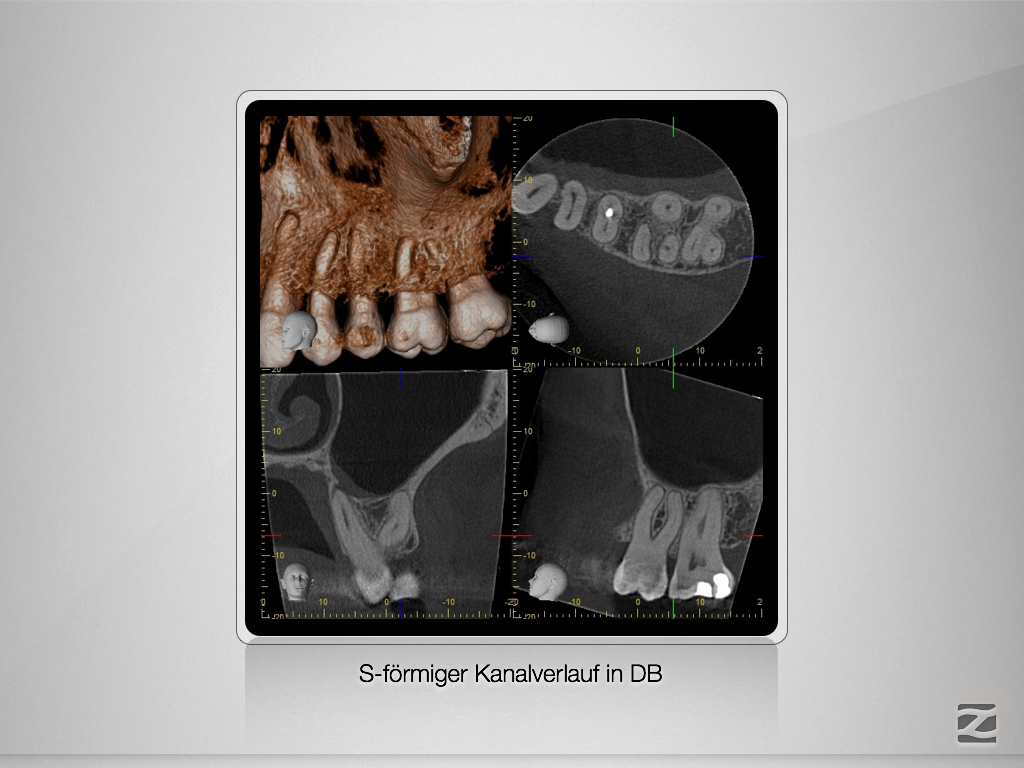

X-Bein- mit Überlegung zum Erfolg